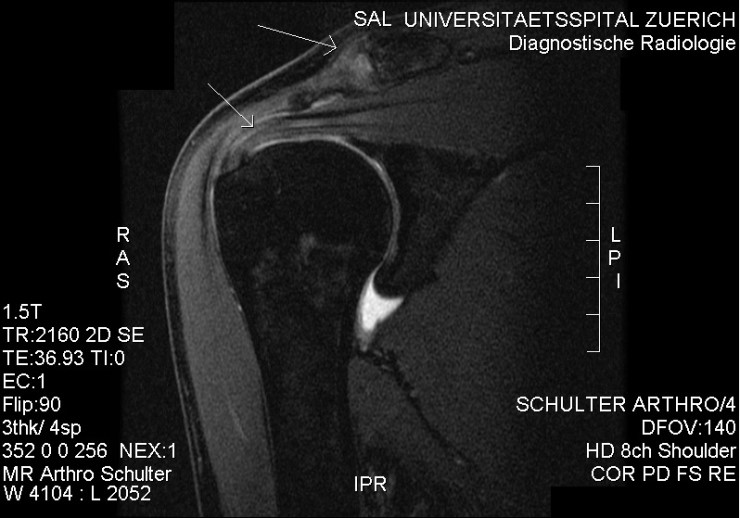

Q=어머니는 오랫동안 어깨를 앓고 있었지만, 얼마 전부터 잠자리에서도 어깨 통증에 시달리고 있습니다. 팔도 거두는 것이 큰일이라고 합니다. A=흔히 있는 어깨의 질환으로 충돌 증후군(회전 근개 손상)오십견(유착성 관절 피막염), 석회화 건염, 관절 와진 파열, 근막 통증 증후군 등이 있고 외에도 목과 어깨의 다양한 부위의 신경 압박으로 어깨의 통증이 있습니다. 많은 환자들이 이렇게 말하고 있습니다. “여러 병원·의원에서 뢴트겐(X선)을 찍고 이상이 없는 주사를 맞아 물리 치료를 했지만 별로 효과가 없어 그 때만 증세가 더 심해지는 것 같아요.”X선에서는 뼈 이외의 무수한 구조물을 볼 수 없습니다. 골절에 의한 어깨 통증 외에 엑스 레이로 보이는 어깨 통증의 원인은 골암와 석회화 건염 뿐입니다. 그러므로 외상이 없을 때는 X선 검사는 필요 없다고 생각합니다. 많은 분들이 장기간 충돌 증후군의 치열한 인대 손상을 주사와 물리 치료에만 의존했으나 수술 시기를 놓쳐서 심한 관절염으로 팔을 쓰지 못한다 아쉬운 경우를 자주 봅니다. 어깨의 회전통과 활막이 어깨 관절을 안정시키는 유일한 구조물입니다. 그래서, 인대 손상과 어깨의 회전통이 심한 위축이 오면 어깨 관절이 불안정해지면서 장기적으로 치열한 관절염에 진행되고 팔을 못쓰게 될 뿐 아니라, 아파서 잘 수 없게 됩니다. 진찰시에 충돌 증후군이 의심스러우면 꼭 자기 공명 영상(MRI)검사를 해야 합니다. MRI영상으로 힘줄 손상 정도로 근육의 퇴화 정도를 보며 수술 여부를 정합니다. 그래서 미국의 상당수 주에서 MRI검사 없이는 관절경 수술을 금지하고 있습니다. -영상 의학과 의원(소죠은데 원장)-

Q=어머니는 오랫동안 어깨를 다치셨지만, 얼마 전부터는 잠자리에서도 어깨 통증으로 고생하고 계십니다. 팔도 올리기 힘들대요. A=흔히 흔한 어깨질환으로 충돌증후군(회전근개손상), 오십견(유착성관절막염), 석회화건염, 관절와순파열, 근막통증후군 등이 있으며 이외에도 경추나 어깨 여러 부위의 신경압박에 의한 어깨통증이 있습니다. 많은 환자들이 이렇게 말합니다. 여러 병의원에서 엑스레이(X-ray)를 찍고 이상이 없어 주사를 맞고 물리치료를 했는데 별 효과가 없고 그때만 증상이 더 심해지는 것 같아요. 엑스레이에서는 뼈 이외의 무수한 구조물을 볼 수 없습니다. 골절에 의한 견통 외에도 엑스레이에서 볼 수 있는 견통의 원인은 골암과 석회화 건염뿐입니다. 그렇기 때문에 외상이 없을 때는 엑스레이 검사는 필요 없다고 생각합니다. 많은 분들이 장기간 충돌증후군으로 인한 극심한 인대 손상을 주사와 물리치료에만 의존하다가 수술 시기를 놓쳐 심한 관절염으로 팔을 사용할 수 없게 되는 안타까운 경우를 자주 봅니다. 어깨 회전근과 활막이 견관절을 안정시키는 유일한 구조물입니다. 따라서 인대 손상과 어깨 회전근의 심한 위축이 오게 되면 견관절이 불안정해지고 장기적으로 심한 관절염으로 진행되어 팔을 사용하지 못하게 될 뿐만 아니라 아프고 잠을 잘 수 없게 됩니다. 진찰 시 충돌증후군이 의심되면 반드시 자기공명영상장치(MRI) 검사를 해야 합니다. MRI 영상에서 힘줄 손상 정도와 근육 퇴화 정도를 보고 수술 여부를 결정합니다. 따라서 미국의 많은 주에서 MRI 검사 없이는 관절경이나 수술을 금지하고 있습니다. – 영상의학과의원(서정대원장)-